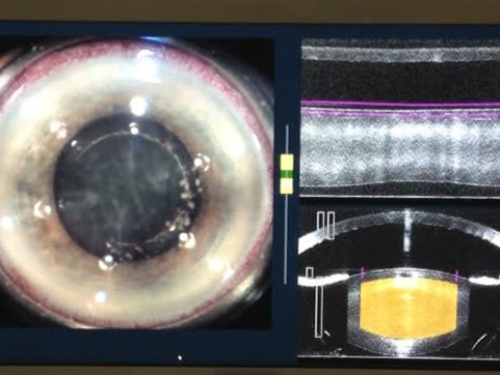

Procédure de découpe du cristallin au laser femtoseconde avant l'étape de la chirurgie proprement dite

Pour la cataracte, le laser femtoseconde est une étape au préalable préparant la chirurgie de la cataracte. Ce laser représente une aide pour le chirurgien permettant de réaliser en amont des étapes de la chirurgie au laser de manière automatisée et reproductible.

Les incisions de la cornée et la découpe du cristallin seront ainsi réalisés par le laser à la place du bistouri et de la pince.

Après la procédure au laser, le chirurgien opère la cataracte mais avec des étapes en moins et aura besoin de moins d'ultrasons pour extraire le cristallin.